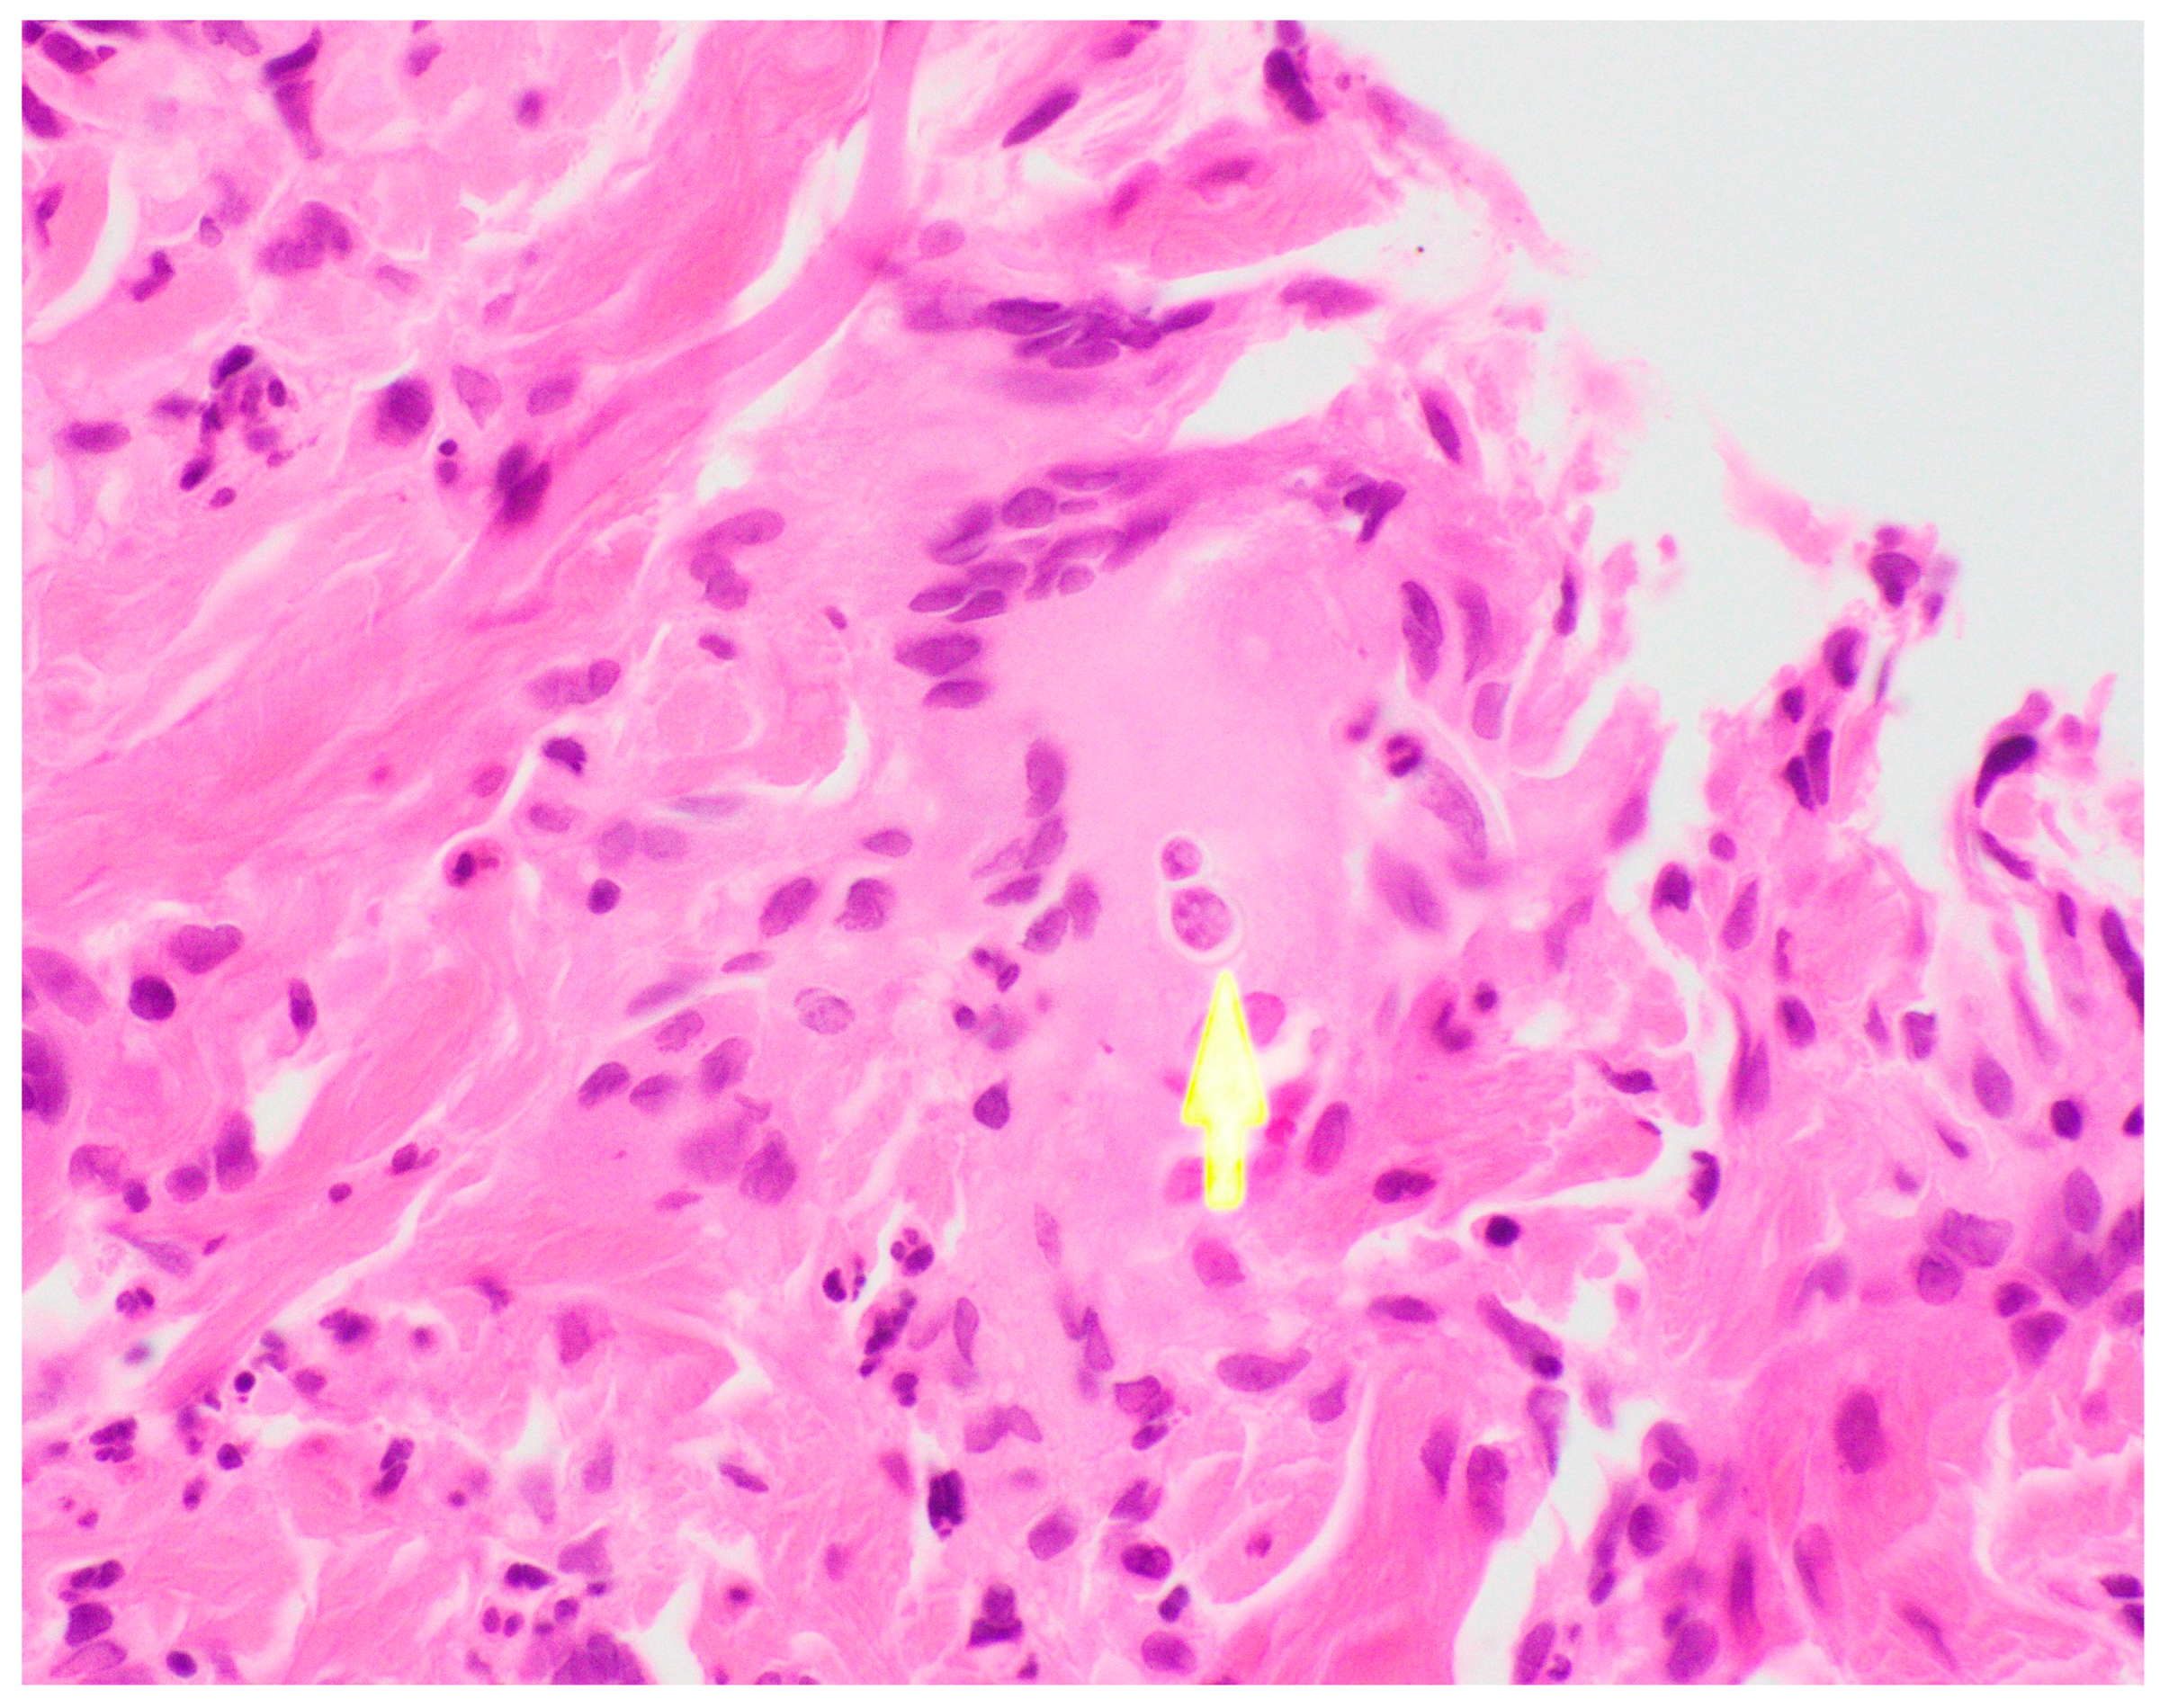

Ultimately, a punch biopsy of his left second metacarpophalangeal joint was taken in addition to cultures from the left hip sinus tract drainage which revealed the presence and growth of Blastomyces dermatitidis, respectively (Figure 4 and Figure 5). Serology testing was also ordered, which was positive for Blastomyces antibody immunodiffusion (ID), though negative for Blastomyces antibody complement fixation (CF). Notably, a urine histoplasma antigen test was positive with a result of > 25.0 ng/mL with a negative histoplasma antibody ID test, likely indicating a component of cross-reactivity in the presence of Blastomyces dermatitidis.

Figure 4. Left 2nd MCP Joint.

Figure 5. Left 2nd MCP Biopsy (H&E).